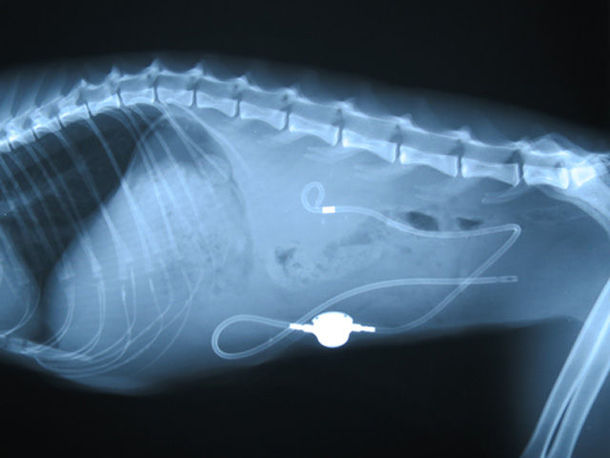

今回の手術は大変高度な技術と高価な器具を使用した緊急手術で、腎臓から膀胱を繋ぐ「SUBシステムの設置」をする手術でしたが、 手術と入院代で65万円が必要で、費用の一部をご支援いただきたいと思っています。

このSUBシステムの設置手術は、ここ5年ぐらいで日本で採用され始めた非常に新しく、高度な技術を要する手術だそうです。設備が整った病院でないとできない手術でしたが、モモは幸いその様な病院、獣医師さんに巡り会えたのです。

細かい処置まで含めると6時間近くの大手術となりましたが、無事に成功しモモも目覚め、現在は通院での治療を継続中です。

このSUBシステムは数ヶ月に一度洗浄が必要で、モモはこの先ずっと、この器具とつき合っていく事になりました。器具を体内に入れた事により、体の中で異物反応が起こったり、膀胱炎、細菌感染、アレルギー反応など、今後も様々な事も予測されます。